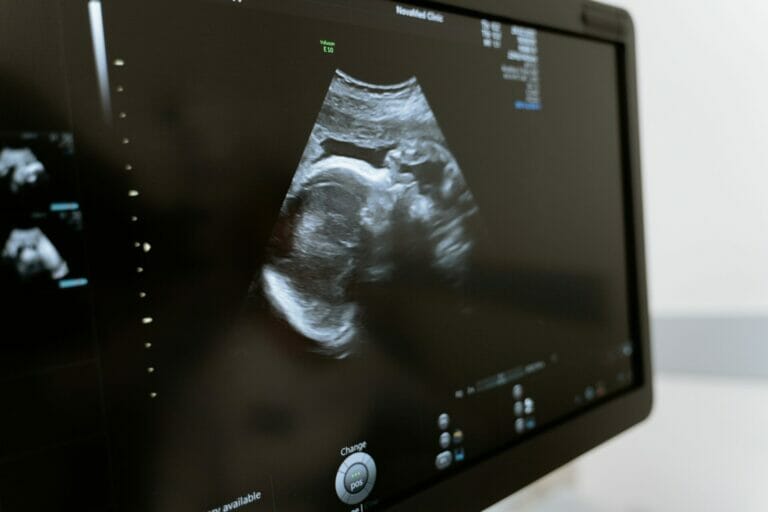

الأسبوع الثالث والعشرون من الحمل في الأسبوع الثالث والعشرون من الحمل تطورت ملايين من خلايا الدماغ في مخ طفلك على مدار الأسبوعين المقبلين، وستتحكم في جميع حركات طفلك وحواسه ووظائف الجسم الرئيسية مثل التنفس. قد…